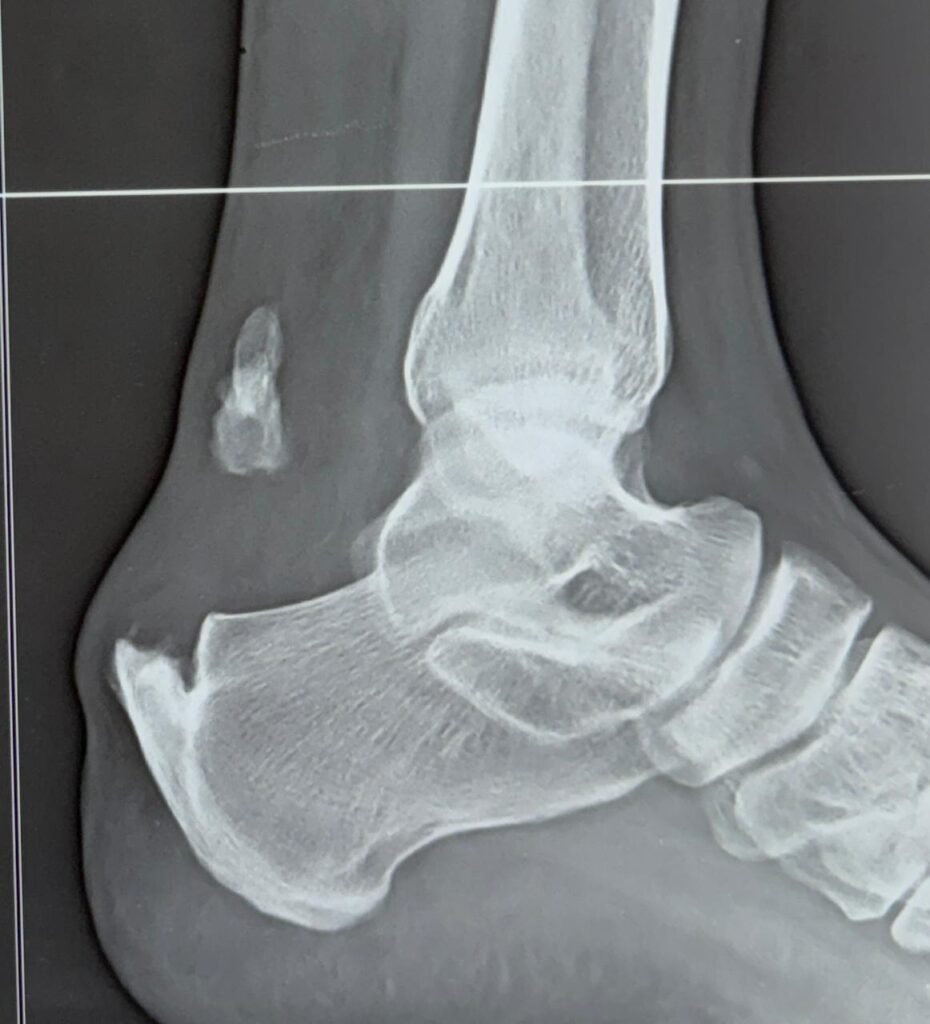

Minimal invasive calcaneum fracture surgery                                </p>

Minimal invasive calcaneum fracture surgery

Minimal invasive calcaneum surgery repairs heel fractures with small cuts, less pain, and quicker recovery.